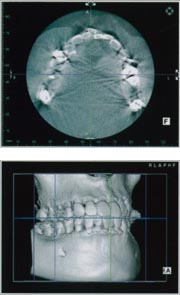

![]() Computed Tomographyの略で、通常はX線を用いて生体の断層像を得るX線CTをさします。 「物体の内部構造は、その物体を複数の方向から投影して得られた情報から再構成することができる」という基本原理に基づいている。 実際には生体のある断面に多方向から幅の狭いX線ビームを曝射(ばくしゃ)し、 透過したX線を検出してその断面内でのX線の吸収の度合いの空間分布をコンピュータで計算し画像化している。 人体の最初のCT画像は1972年にイギリス放射線学会でハウンズフィールドGodfrey N. Hounsfield(1979年ノーベル医学生理学賞受賞)により、 computerized axial transverse scanningという名称で発表された。それ以来、X線によるスキャン方法と検出系さらに画像再構成技術の開発進歩により、 空間分解能と濃度分解能に加え時間分解能にも優れた断層撮影法として、CTは全身の画像診断に革命的な進歩をもたらしています。 |

![]() インプラントの治療には正確な距離計測が必要となります。 CT撮影により正確な距離を計測します。 |

![]() 三次元構築し、全体を把握します。 |

![]() 個々の部位の計測を行い、各部位を精確に診断していきます。 |

![]() 最先端技術であるインプラントおよび歯科矯正治療を行うためにCTは必要不可欠です。 |